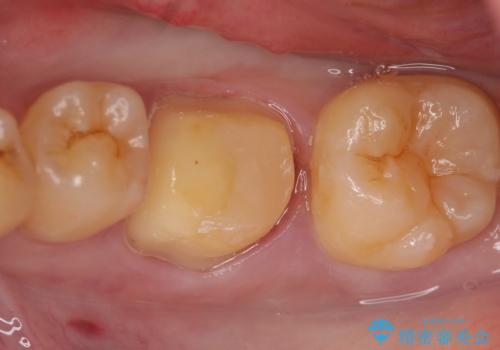

虫歯除去後、オールセラミッククラウンによる補綴を行いました。

今回用いたオールセラミッククラウンはジルコニアフレームという白い素材の上にセラミックを盛っているため、審美性が非常に高いのが特徴です。

また、ジルコニアは人工ダイヤモンドの材料にも使われているほど高い強度を持っており、そのためオールセラミッククラウンは審美性だけでなく、奥歯やブリッジの補綴も可能とするクラウンです。